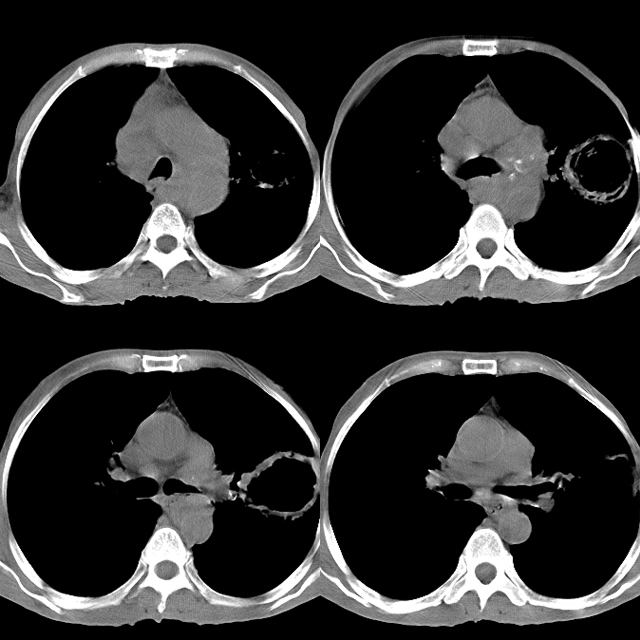

以下是引用心路寻觅在2010-4-17 18:35:00的发言:[br]纵膈多组淋巴结肿大呈“冰冻纵膈”,左肺上叶空洞伴其内结节密度影,考虑淋巴瘤伴左肺上叶曲霉菌感染。[br][br][本贴已被 心路寻觅 于 2010-4-17 18:36:23 修改过]

以下是引用zhangzhongshou在2010-4-17 19:32:00的发言:[br]一元论考虑左肺空洞型肺癌并纵隔淋巴结转移可能性大。